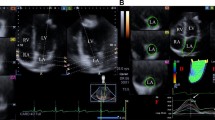

3D-STE has been developed with the aim of overcoming the technical limitations associated with 2D-STE. This technique allows tracking of speckle patterns that move out of the imaging plane. A novel myocardial deformation parameter, 3D tangential strain (3D-TS), which is defined as the greater of the 2 deformation values along the 2 diagonals of the quadrangular endocardial units formed by the analysis software (Fig. 1),could also be calculated with this modality [4]. Several studies, the largest being the NORRE study by the European Association of Cardiovascular Imaging (EACVI), have evaluated the LVS patterns by 3D-STE in healthy adults. Reference ranges in healthy adults were proposed, and age and gender-related distribution patterns of these parameters were described [5, 6].

4D LV-analysis package of the Tomtec software was used for 3D-STE analysis. The software processed the 3D full volume dataset and produced the 2, 3 and 4 chamber views automatically. In the respective panels displaying these views, an axial line segment was aligned by the operator manually so that it was positioned between the center point of the mitral annulus and the LV apex. The software automatically traced the LV endocardium frame-by-frame in the next step. Manual corrections were made on the automatically traced endocardial borders as needed, in the end-systolic and end-diastolic frames. Finally, the software gave the peak and end-systolic 3D-TS, 3D-GLS, 3D-GCS, 3D-GRS, twist and torsion values as well as 3D-LVEDV, 3D-LVESV and 3D-LVEF. The analysis software derives the radial strain measurements from the endocardial area, according to the principle of volume conservation. Circumferential strain is derived from the endocardial border [13]. Tracking quality was classified as excellent, good or fair, and the signal to noise ratio was classified as good or bad, subjectively by the operator. 3D-STE analysis was defined as feasible when all the strain parameters were retrievable and the number of poorly tracking or non-tracking segments was ≤ 2 (Fig. 2) [4].